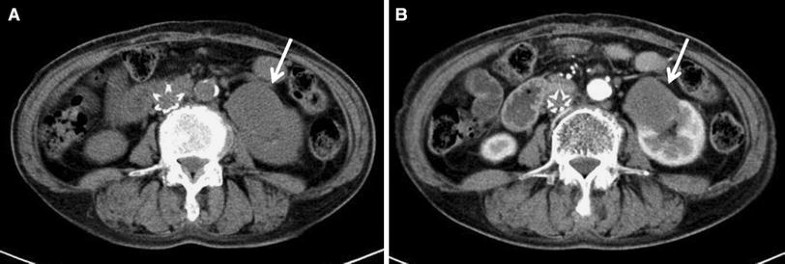

Abdominal computed tomography revealed a hypovascular tumor (4.3 × 3.5 × 4.6 cm) (arrow) in the lower pole of the left kidney (a plain, b enhanced)